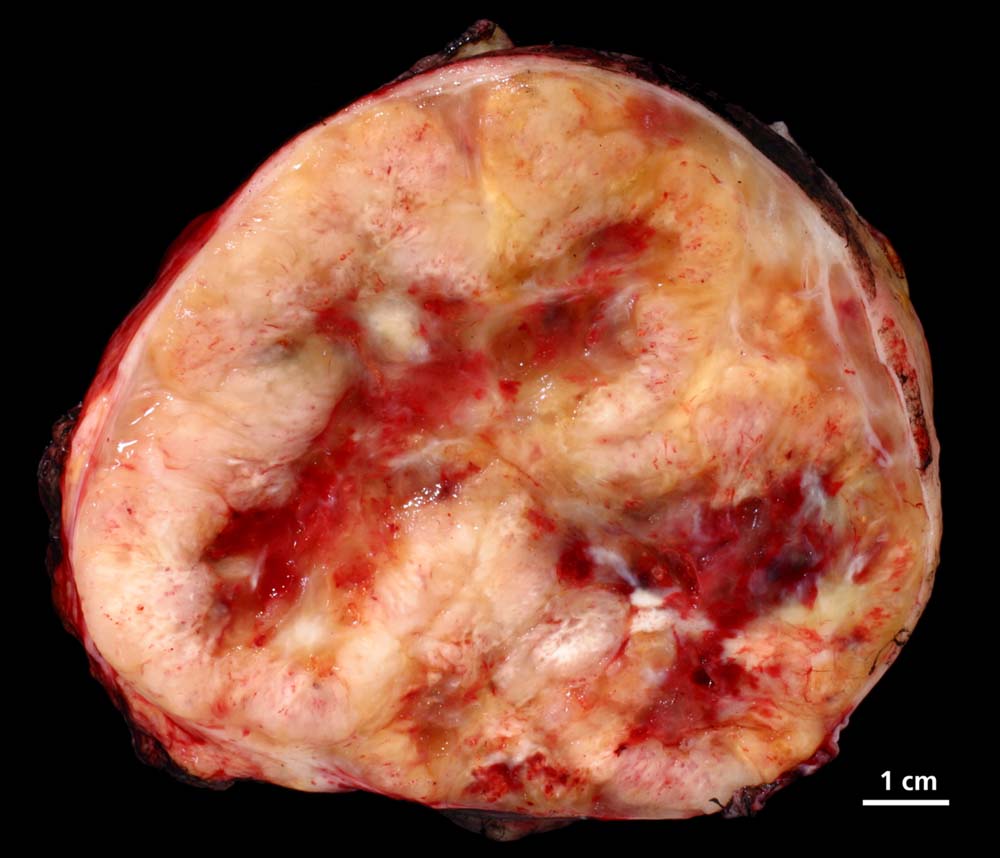

Makroskopisch imponieren Schwannome als scharf begrenzte, derbe, teils zystische Tumoren mit einer Grösse von bis zu 10 cm. Einblutungen sind möglich. Ausser bei Lokalisation im Knochen, in viszeralen Organen oder der Haut sind Neurinome meist abgekapselt. Gelegentlich erkennt man im Randbereich des Neurinoms Anteile des zur Seite verdrängten peripheren Nerven. In peripheren Tumoren lässt sich aber in weniger als der Hälfte der Fälle ein assoziierter Nerv identifizieren. Im Gegensatz zum Neurofibrom, welches den betroffenen Nerven infiltriert, lassen sich beim Schwannom intratumoral keine axonalen Strukturen nachweisen (Holmes Luxol Färbung).

Makroskopie